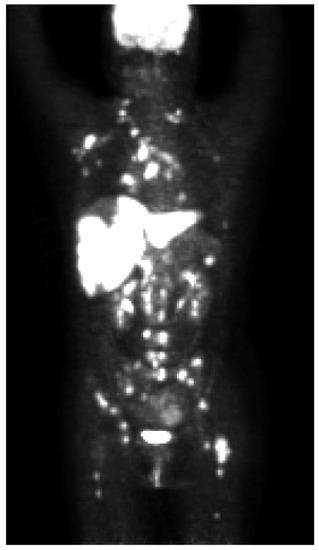

Successful Alectinib Treatment for Carcinoma of Unknown Primary with EML4-ALK Fusion Gene: A Case Report

2. Case Presentation